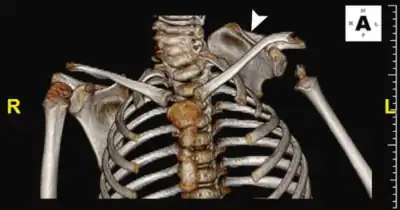

Klippel–Feil syndrome (KFS), also known as cervical vertebral fusion syndrome, is a rare congenital condition characterized by the abnormal fusion of any two of the seven bones in the neck (cervical vertebrae).[1]: 578 It results in a limited ability to move the neck and shortness of the neck, resulting in the appearance of a low hairline.[2]

KFS is usually diagnosed after birth. The most common signs of the disorder are restricted mobility of the neck and upper spine and a shortened neck with the appearance of a low hairline at the back of the head.

- Sprengel's deformity

- Type I — Fusion of C2 and C3 with occipitalization of the atlas. In 1953, further complications were later reported by McRae; flexion and extension is concentrated within the C1 and C2 vertebrae. As with aging, the odontoid process can become hypermobile, narrowing the space where the spinal cord and brain stem travel (spinal stenosis).

- Type II — Long fusion below C2 with an abnormal occipital-cervical junction. Similar to the C2-C3 fusion of McRae and could be viewed as a more elaborate variation. Flexion, extension, and rotation are all concentrated in the area of an abnormal odontoid process or poorly developed ring of C1 which cannot withstand the effects of aging.

- Type III — A single open interspace between two fused segments. Cervical spine motion is concentrated at single open articulation. This hypermobility may lead to instability or degenerative osteoarthritis. This pattern can be recognized as the cervical spine is often seen to be at an angle or hinge at this open segment.